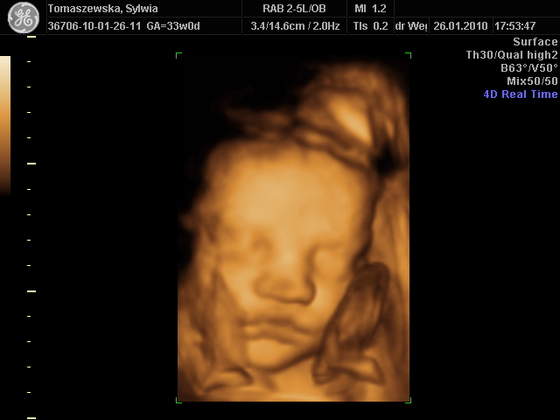

Nasze maleństwo waży 2,5 kg

Wczoraj 33tc 2 dzien Marcysia miala miedzy 2500-2700Czy to prawda ze nasze maluszki teraz tygodniowo beda miedzy 100-200 gram przybierac ? tak pisze w gazecie